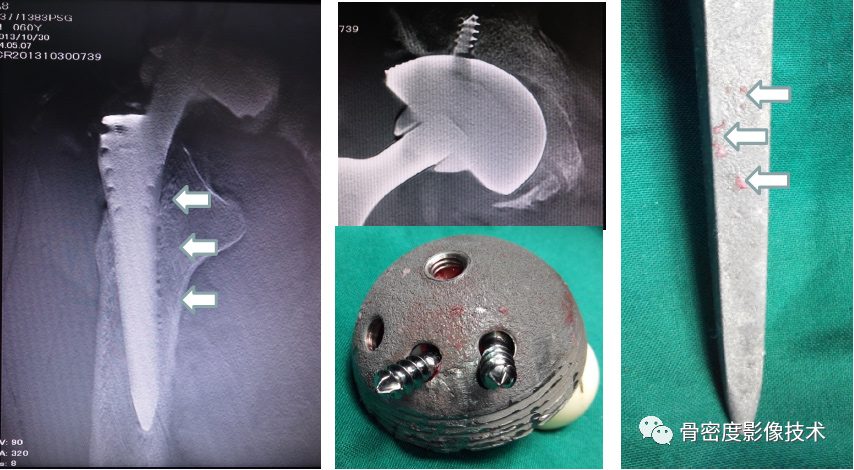

应用适应症:全下肢摄影—人工髋关节、膝关节置换以及下肢不等长畸形的矫正和O、X型腿畸形的矫正。可进行骨密度检查和负重全下肢扫描。

图5 股骨颈骨质量术前评估联合股骨、膝关节置换等术后评价

图6 髋臼骨质量术前评估联合臼杯置换术后评价

备注:图片由北京积水潭医院提供